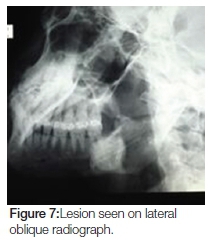

Panoramic, lateral oblique and cone-beam radiographs were taken, all of which revealed a large radiopaque lesion apical to the 48. This confirmed the presence of a sialolith (Figures 6, 7, 8, 9).

The lesion on cone-beam was seen to measure 25 x 26 mm in diameter (Figure 10). This, according to modern literature, would be considered a giant sialolith.